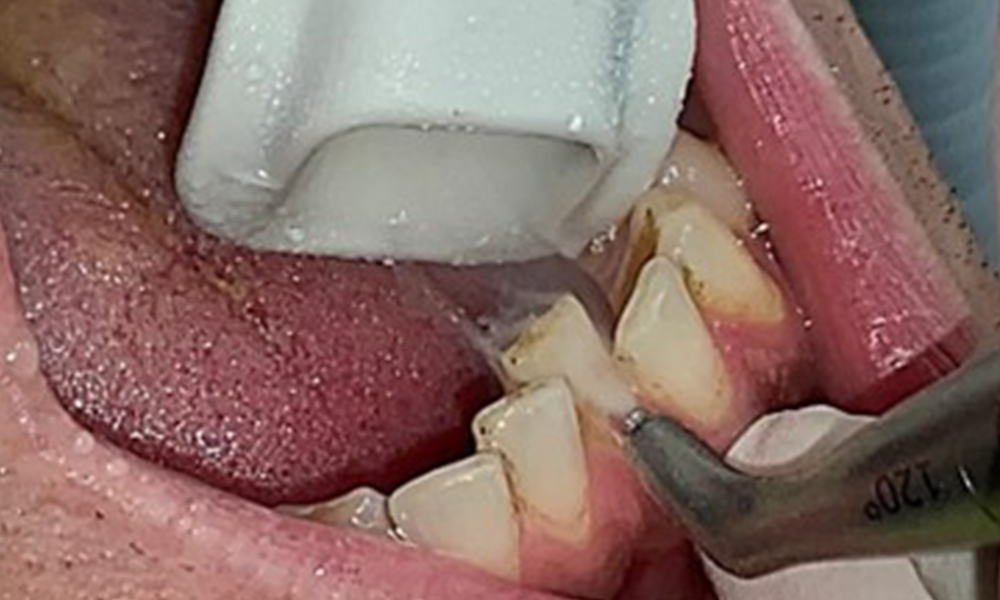

Close-up view of teeth

Fig. 5: Close-up view of teeth 45 to 47. The green arrows show dental attrition and erosions of the buccal cusps with partial enamel loss, © Dr R. Krapf

The objective would be to control disease risk by removing supragingival and subgingival biofilm. The instruments can be selected based on patient needs. First, calculus and any concretions must be removed using ultrasonic and/or manual instruments (Fig. 10).

Use of a piezo-driven ultrasonic device in the lingual area near 36 (Proxeo Ultra, W&H, shown here)